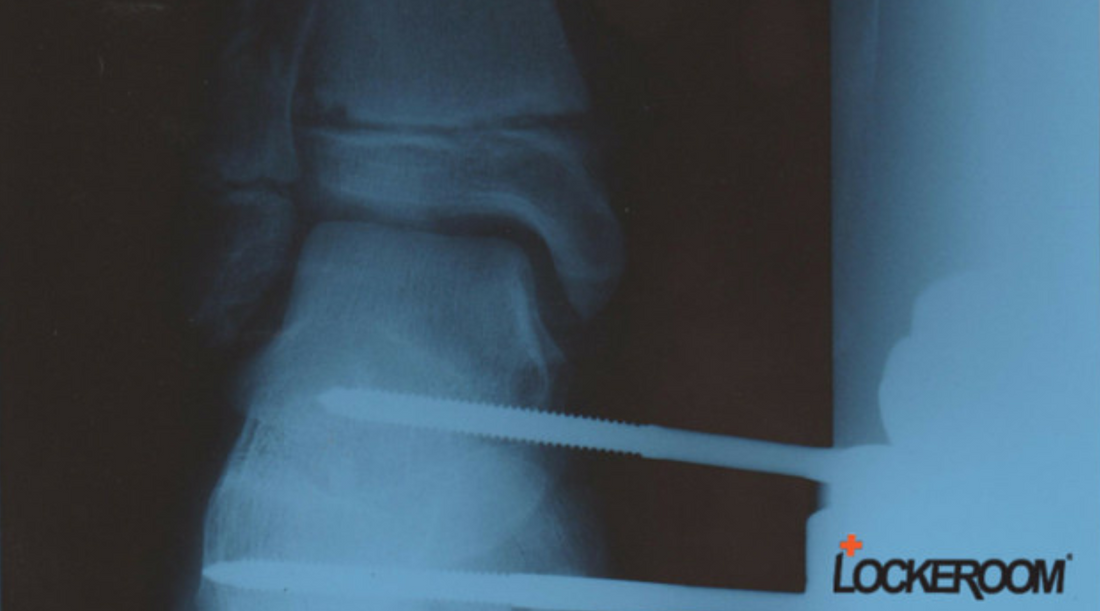

This diagnostic image clearly shows a fracture. As a Physiotherapist, this type of information is presented to me by patients, daily.

What the image doesn't tell is that it was a medial compound fracture of the tibial growth plate of a 14 year old boy caused when he fell from a flying fox (although the screws of the external fixator should be a give away!)

I know, because this is an X-ray of my son's leg and I was there when he broke it.